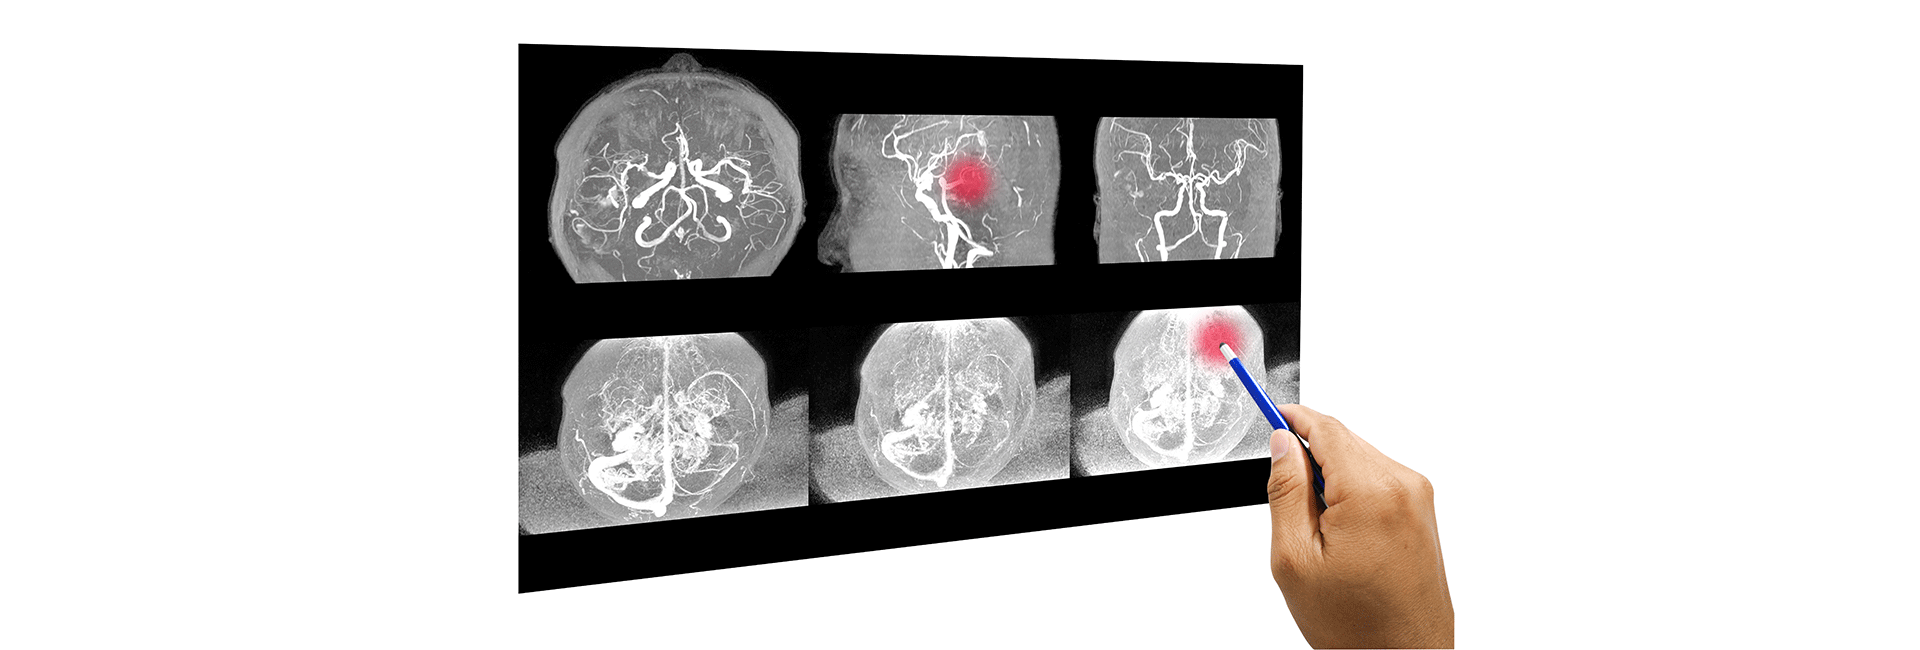

Preoperative tumour embolisation is used when a brain or spinal tumour is fed by many tiny blood vessels and would likely bleed heavily during surgery. The aim is not to remove the tumour itself, but to reduce its blood supply before the neurosurgeon operates. That preparation can make the surgical field clearer, the procedure more controlled, and blood loss significantly lower.

The process begins with detailed angiographic imaging. This maps the vessels feeding the tumour and shows which arteries can be safely targeted. The interventional radiology team studies the anatomy carefully because vascular tumours can be supplied by several small branches, and each one may behave differently. Good planning here matters just as much as the embolisation itself.

On the procedure day, the patient is placed under monitored anaesthesia or sedation. A thin catheter is advanced through a blood vessel, usually from the groin or wrist, and guided into the arteries supplying the tumour. Once the catheter is in position, the specialist injects tiny particles such as PVA or microspheres, or sometimes a liquid embolic agent, to block the blood flow feeding the mass.

Over time, the devascularised part of the tumour begins to soften or necrose, which reduces bleeding risk during the next surgery. In many cases, the neurosurgeon can remove the tumour more safely and efficiently after embolisation. That is why tumour embolisation in Kanakapura Road, Bangalore is often considered an important bridge between diagnosis and definitive surgical treatment, especially for highly vascular lesions like meningiomas or paragangliomas.